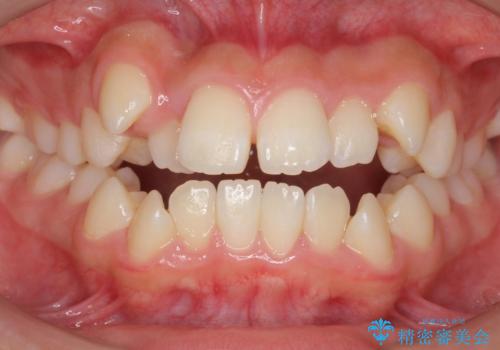

気になるデコボコとオープンバイト インビザラインでの矯正治療